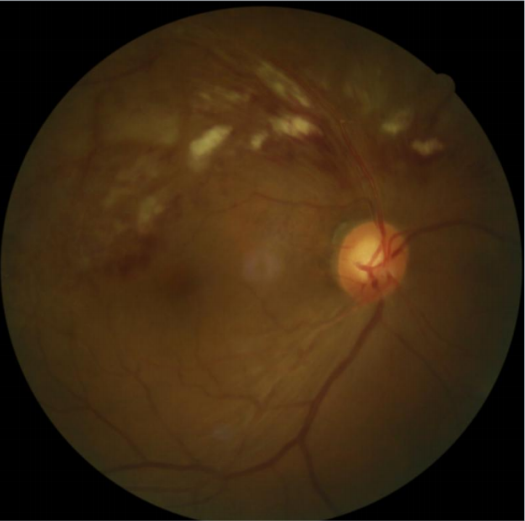

患者刘某,58岁,因右眼视力下降伴变形1月入院。既往有高血压病,血糖偏高病史,左眼视物不见10余年,经过眼科主治医师方霏的详细检查及眼底造影检查,发现是患上了右眼视网膜分支静脉阻塞,右眼黄斑水肿,左眼萎缩性黄斑病变。刘大叔入院时右眼视力仅0.1 ,需要使用一种新型的生物制剂(抗 VEGF)治疗,方霏主治医师向患者及家属交待病情、手术必要性及相关风险 ,在排除了手术禁忌症后,患者及家属表示同意手术治疗。次日,方霏主治医师在患者表面麻醉下进行右眼玻璃体药物注射术,术后患者无明显特殊不适。4周后复查,右眼黄斑水肿明显减轻,视力由0.1提高至0.6。玻璃体腔注药术明显改善了患者视力,患者刘大叔表示十分满意。

术后4周眼底照相